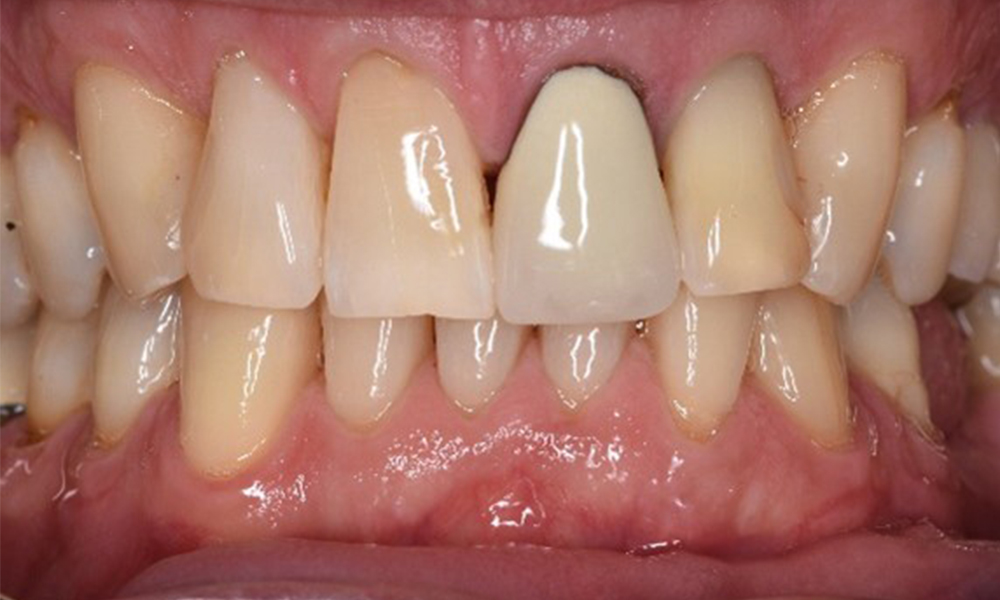

Frontansicht Gebiss (Ober- und Unterkiefer)

Frontansicht